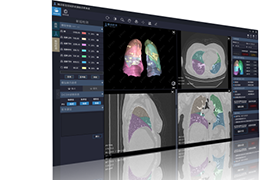

ART-Plan™ Artificial Intelligence Contouring